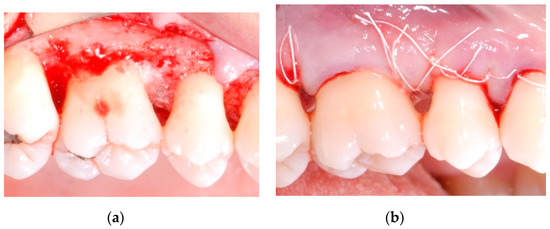

Periodontal parameters were collected at first visit, at re-evaluation after initial therapy, before surgery (baseline) and 12 months after the surgical procedure. The gingival index (GI) and plaque index (PI) were recorded [26], while probing depth (PD) and clinical attachment level (CAL) were measured at 6 sites per tooth (mesio-buccal, mid-buccal, disto-buccal, disto-lingual, mid-lingual, mesio-lingual) by using a periodontal probe (PCP-UNC 15, Hu-Friedy, Chicago, IL, USA) (Figure 4a). Measurements were rounded to the nearest millimeter. When the cemento-enamel junction (CEJ) could not be used for determining CAL, the restoration margin was used as a reference [27]. The site presenting the deepest PD was included in the final analysis.

Figure 4.

(a) Probing depth (PD) and clinical attachment level (CAL) measurement; (b) Intrabony defect depth (IDD) was defined as (CEJ-BD)—(CEJ-AC); CEJ: cement enamel junction; BD: bottom of the defect; AC: alveolar bone crest.

All the clinical measurements were taken by three independent assessors, blinded to treatment assignment. Periapical digital radiographs were taken using a long-cone paralleling technique with a Rinn-type film holder, before surgery and at 12-month follow-up. The following linear measurements were taken by a single calibrated examiner, on a 30-inch led-backlit color diagnostic display, using measuring software (Image J 1.52a, National Institutes of Health, Bethesda, MD, USA): (1) distance from the CEJ to the most apical extension of the bony defect (CEJ-BD); (2) distance from the CEJ to the most coronal extension of the alveolar bone crest (CEJ-AC). The depth of the intrabony component of the defect (IDD) was defined as (CEJ-BD)—(CEJ-AC) (Figure 4b).